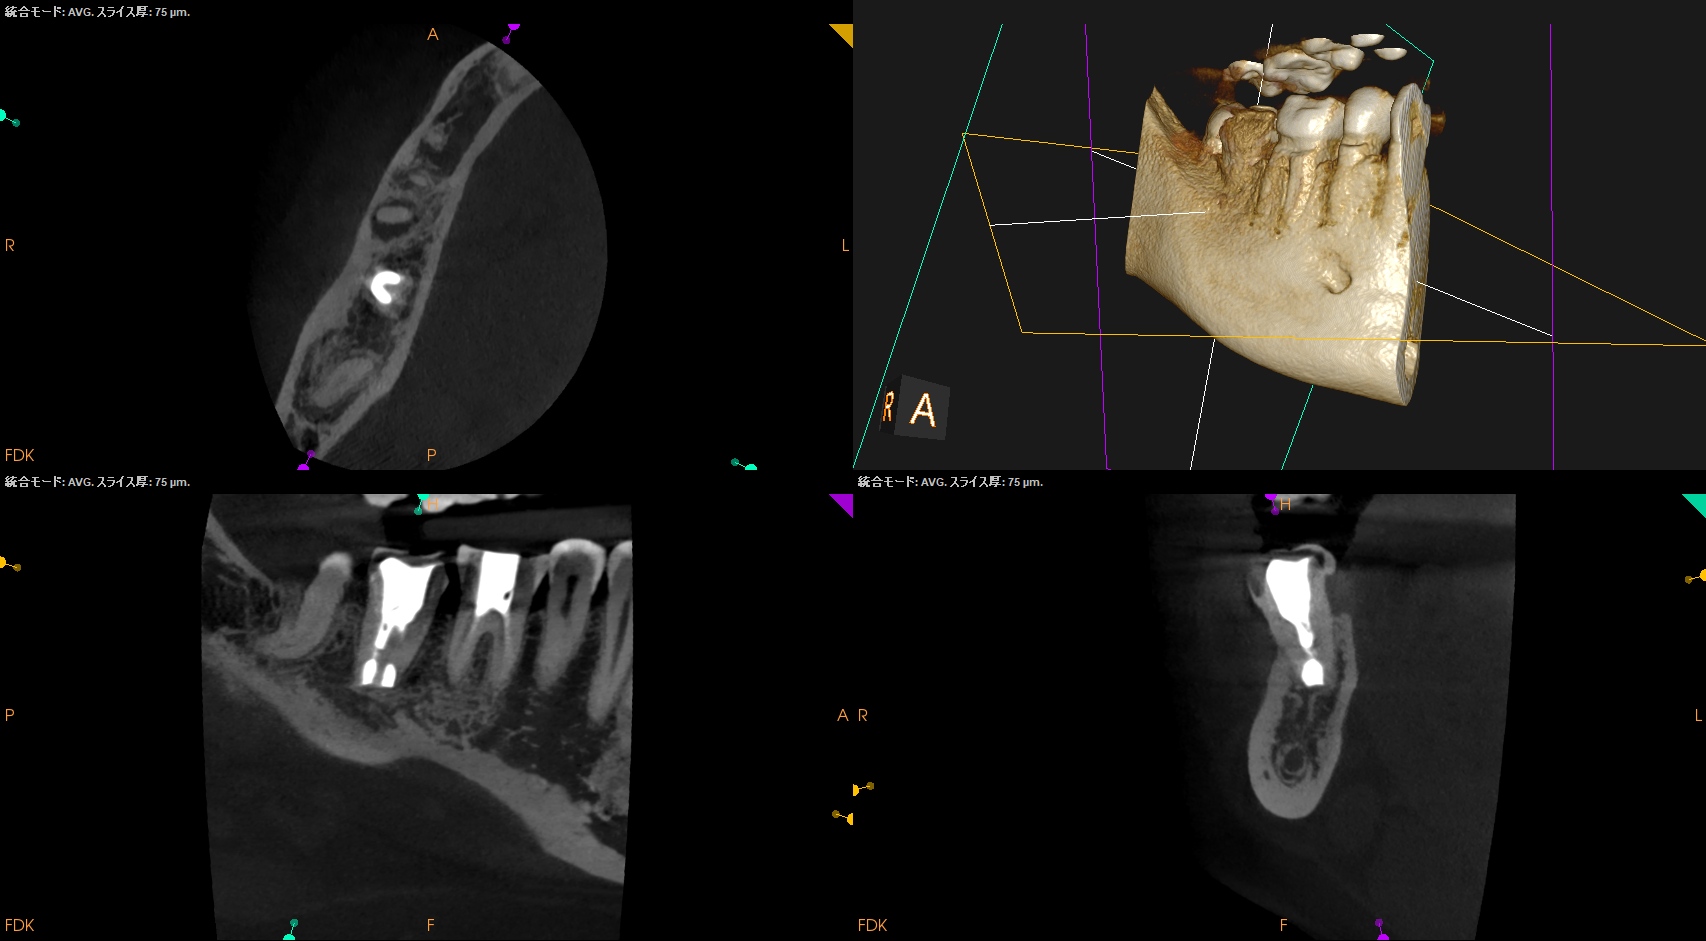

#31 Intentional Replantation 1yr recall(2025.11.28)

術前の臨床症状は消失していた。

初診時と比較した。

劇的に治癒していることがわかる。

打診検査時のアンキローシス音もないことから、この日で終診とさせていただいた。